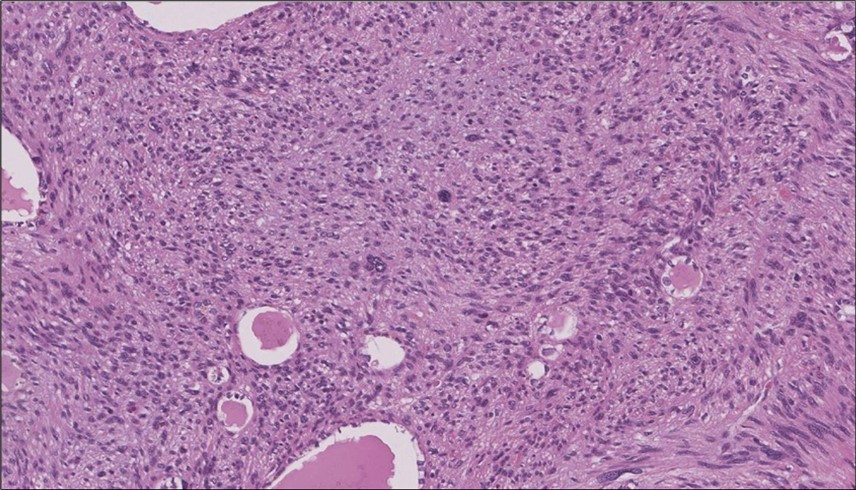

When diagnosing thyroid swelling, imaging studies have been helpful in differentiating malignant from benign tumors with US being used as an initial evaluation tool when assessing thyroid nodules. Tumors are categorized based on composition, echogenicity, shape, margin and echogenic foci into added scores determined by the TI-RADS system, which determines the need for FNA 13. Other imaging modalities include MRI and CT. However; radiological assessment does not distinguish between the types of thyroid cancer, and therefore FNA and biopsy are of crucial importance 3, 6. On a pathologic sample, LMS appears as spindled eosinophilic cells with elongated blunt-ended or cigar-like nuclei arranged in fascicles 2, 7 (Figure 1, Figure 2, Figure 3). Despite the unique microscopic morphology, LMS cannot be distinguished from other spindle cell tumors such as spindle cell variant of medullary thyroid cancer, anaplastic thyroid

Figure 3.Left thyroid The malignant looking cells are showing diffuse atypia, mitosis and hyper-chromatic nuclei, some remaining follicles could be noted as well (H&E, ×400).

cancer, or other metastatic tumors without further testing with genetic or molecular studies 3, 7. Immunohistochemical testing plays a vital role in differentiating LMS from such similar tumors as it stains positive for vimentin and smooth muscle actin (SMA), and is variably positive for HHF35, desmin (50%-100%), and H-caldesmon 3, 6. Moreover, there were no reported cases where thyroid LMS stained positive for thyroglobulin, cytokeratin, calcitonin, chromogranin, or protein S100 3. Our patient’s left thyroid biopsy showed the characteristic microscopic features and was positive for SMA, desmin, caldesmon, P63 with patchy EMA (Figure 1, Figure 2, Figure 3, Figure 4) as well as her liver biopsy (Figure 5, Figure 6, Figure 7); whereas her right thyroid showed clear papillary thyroid cancer cell features (Figure 8, Figure 9).